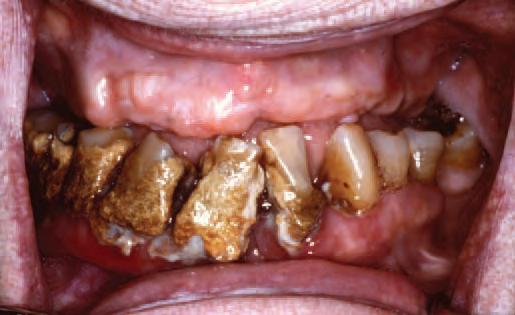

It was very inspiring to see the high-level dentistry presented by the various speakers during the IDA Annual Conference in Killarney. The Conference brought different generations of dentists together, providing us with an opportunity for learning or re-learning, and also socialising with colleagues. It has also put dentistry in the spotlight once more, through the media coverage it received. The front page of the Irish Independent brought to light the shocking news (not new to us) about the lack of dental care for children in Ireland. Children are not being seen in second, fourth and sixth class through the HSE school screening dental service, and some kids are not seen until it might be too late to prevent disease, or save the tooth.

Dental caries disproportionally affects disadvantaged children worldwide, and Ireland is no different. My daughter received a letter for her first dental visit last week: she is nearly 13 years of age. Thankfully she is being well looked after, but what about the thousands of children who may not have the same luck to be protected by good oral hygiene habits, diet and parents’ knowledge? Many of these end up on a general anaesthesia (GA) list to have extractions, meaning pain, reduced quality of life for the child and the parents, lost school days, and lost working days, to name a few of the losses involved.

From a Government perspective, it does not sound like rocket science to me: treating a child under GA costs on average ¤819, which is thought to be as much as eight times higher than the cost of a preventive programme for the same group of patients. A recent toothbrushing pilot programme within the HSE calculated an average cost of ¤14 per child.1 Other countries have done it and proved that it works. Scotland saw a 56% reduction in caries in children’s first permanent molars after two years of implementing a caries preventive programme, and consistent caries reductions were evident four and a half years after the programme ended.